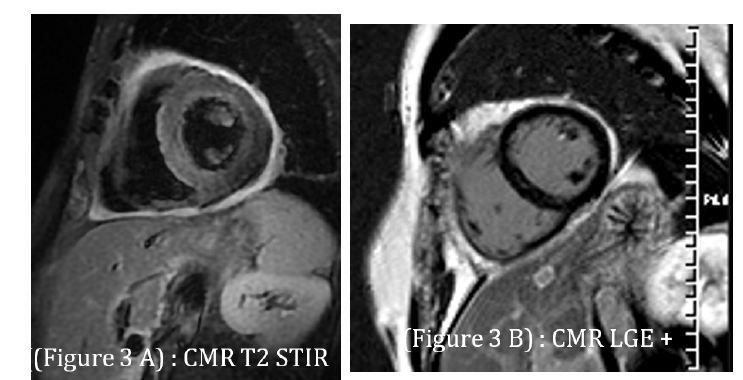

Cardiac magnetic resonance imaging (day 6) showed preserved LVEF (64%), diffuse myocardial edema on T2-weighted sequences, heterogeneous late gadolinium enhancement in the lateral wall, and pericardial thickening with enhancement, confirming acute myopericarditis (Figure 3). At 3-month follow-up, TTE demonstrated preserved LVEF and complete resolution of pericardial effusion.

Fgure 3:Cardiac magnetic resonance imaging: A. T2-weighted image demonstrating diffuse myocardial edema (hyperintensity in lateral wall); B. Late gadolinium enhancement showing patchy subepicardial involvement and pericardial thickening consistent with myopericarditis..